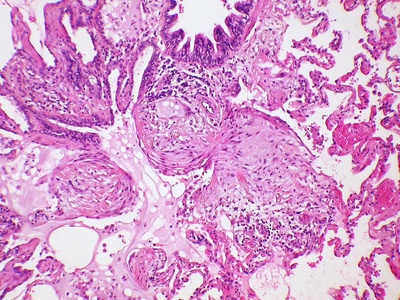

Granulomatous inflammation

Characterized by tight collections of activated macrophages (granulomas) seen in TB, sarcoidosis, some fungal infections, and foreign-body reactions. Tends to form nodules in lungs, lymph nodes, and organs; can cause chronic symptoms and scarring, needs specialist evaluation.